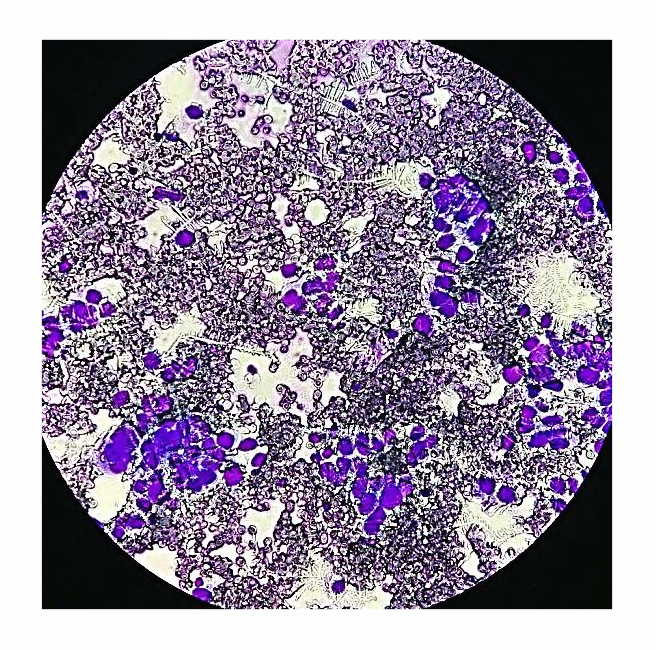

2、痰细胞学:这个检查,把你从肺部咳出的粘液样本(痰)放在显微镜下进行观察看看是否有癌细胞。最好的方式晨起咳痰,连续进行3天的检查。

图片10.png

4、病理活检

图片13.png

如果CT扫描结节或肿块显示有可疑的恶性特性,那么医生将会进行采用以下三种方法对肿瘤进行取样去看看是否有癌细胞(病理诊断),这称为活检。活检包括: